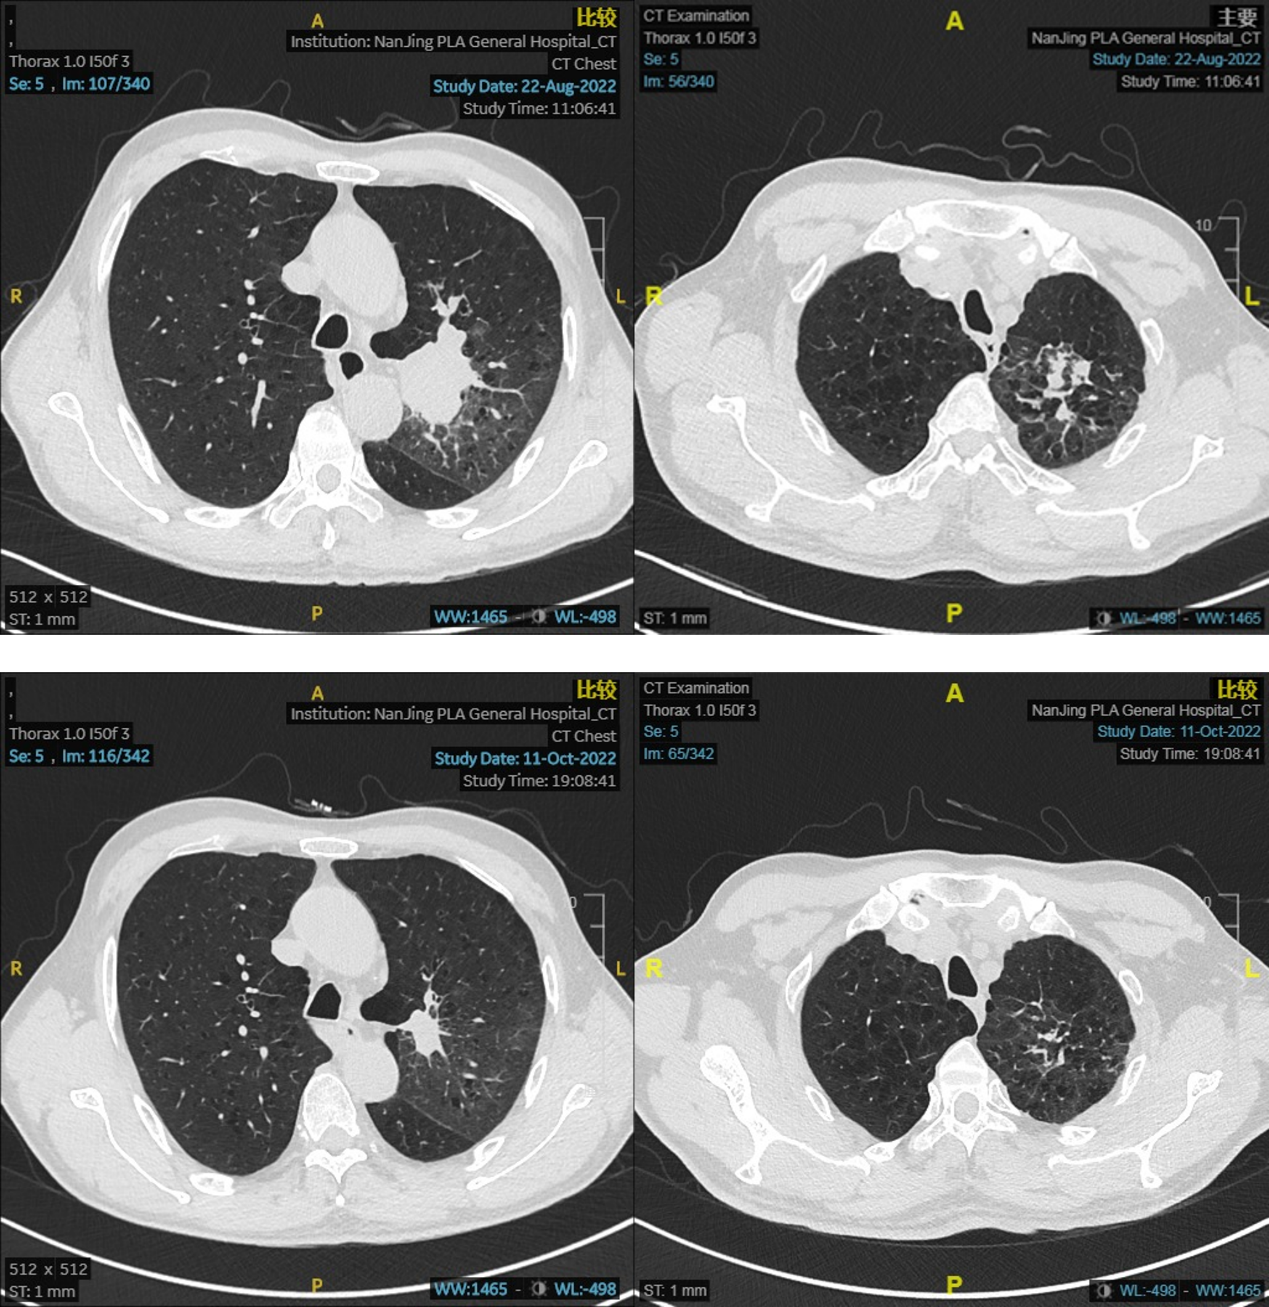

完善PET/MR检查示左肺上叶高代谢肿块伴阻塞性炎症,左肺上叶多发小结节,FDG代谢增高,考虑转移瘤可能;左侧肺门淋巴结,FDG代谢增高,考虑淋巴结转移。

图1 患者基线PET/MR